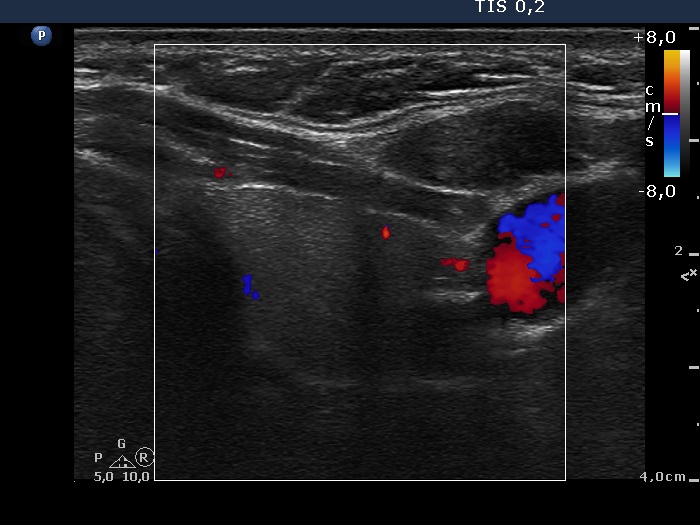

Oxyphilic adenoma - Case 21. (ultrasonographic picture 7)

Left lobe, horizontal scan, color Doppler mode.